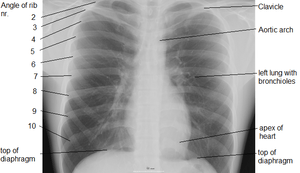

Due to its position separating the thorax and abdomen, fluid abnormally present in the thorax, or air abnormally present in the abdomen, may collect on one side of the diaphragm. An X-ray may reveal this. Pleural effusion, in which there is fluid abnormally present between the two pleurae of the lungs, is detected by an X-ray of the chest, showing fluid collecting in the angle between the ribs and diaphragm.[5] An X-ray may also be used to reveal a pneumoperitoneum, in which there is gas in the abdomen.

An X-ray may also be used to check for herniation.[6]